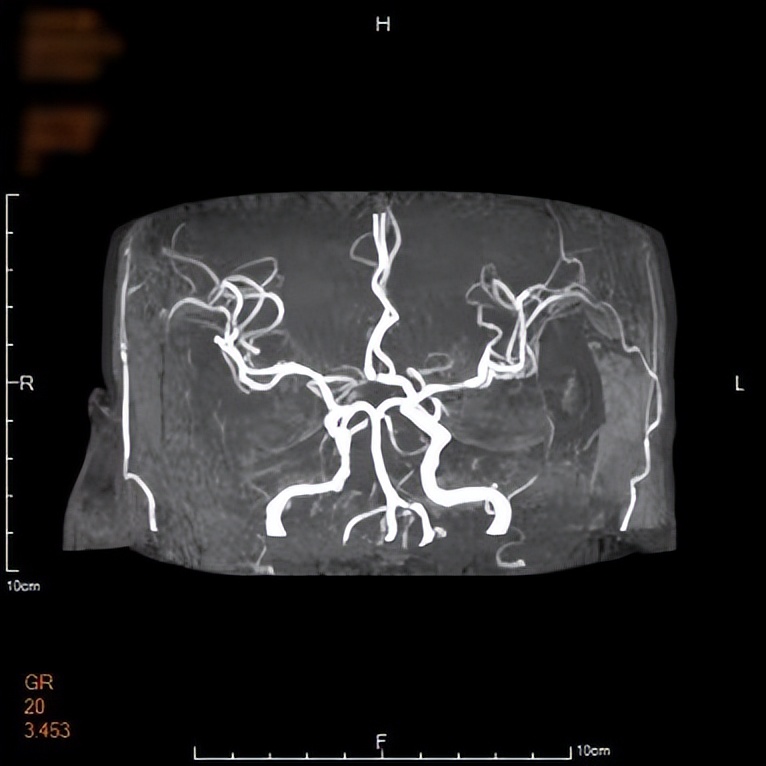

神经内五科医生接诊后完善相关检查,经评估后考虑是脑卒中(俗称中风)。在进一步的头颅磁共振检查中,图像上赫然出现的“心形图案”,印证了最初的猜测,这是脑梗死中罕见的“心形梗死”——双侧延髓内侧梗死(BMMI)。